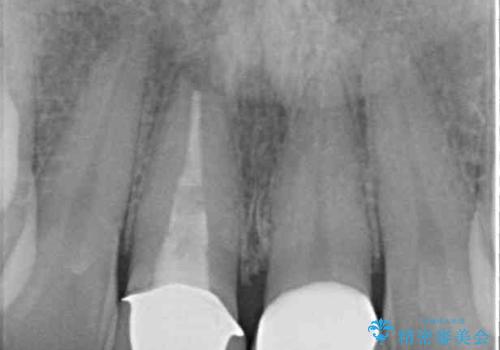

- 前歯のプラスチックが変色していることを気にして来院された患者様です。

反対側同名歯にセラミッククラウンが装着されていたため、そちらのクラウンと形態や色彩を揃えるようオーダーメイドタイプのオールセラミッククラウンにて補綴することとしました。

2本同時に処置をし、2本とも明るい色合いにすることをお勧めしましたが、今回は1歯のみとしました。

左右のバランスが取れ、患者様には大変満足していただきました。